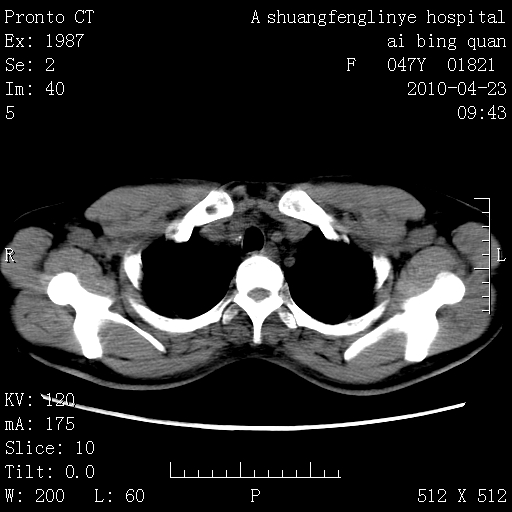

标题: CT25944:胸痛、气短、前几日高烧!肺Ca?请会诊! [打印本页]

标题: CT25944:胸痛、气短、前几日高烧!肺Ca?请会诊!

双肺多发结节,考虑转移瘤,肺癌肺转移不除外

双肺多发结节,部分密度较高,最大结节边缘光滑。临床有“胸痛、气短、前几日高烧”病史。首选考虑:右肺感染性病变!建议积极消炎后复查!

建议抗炎治疗后复查,排除肿瘤性病变。